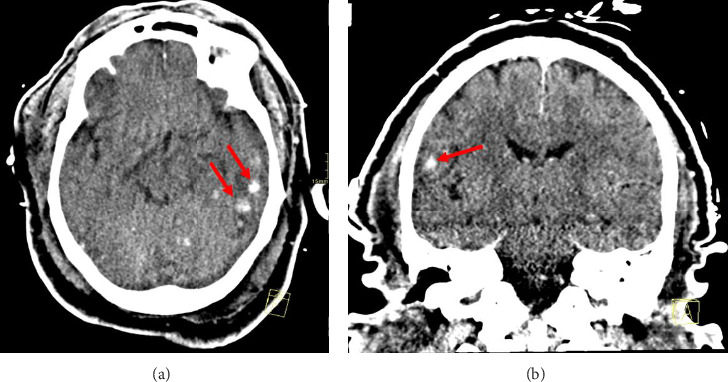

Hemophagocytic lymphohistiocytosis is a fatal hyperinflammatory disorder in which CD8+ cytotoxic T-cells, natural killer cells, and macrophages destroy hematopoietic cells and vital organs. Viral infections, such as Epstein-Barr virus, are known to cause secondary hemophagocytic lymphohistiocytosis in adult patients. However, despite its rarity, dengue virus has been identified to potentially cause hemophagocytic syndrome, which is associated with significant mortality and morbidity. Herein, we present a case report of a 52-year-old male patient who presented with fevers, worsening non-bloody copious diarrhea, excessive fatigue, and nausea and vomiting. He was known to have sickle cell trait. A diagnosis of hemophagocytic lymphohistiocytosis was confirmed with a liver biopsy, accompanied by elevated ferritin levels (33,539 ng/mL), IL-2R levels (5944.2 pg/mL), thrombocytopenia (49 k/μL), anemia (hemoglobin and mean corpuscular volume of 7.3 g/dL and 77.3 fL), and elevated bilirubin (total bilirubin of 3.2 mg/dL). In addition, elevated IgG and IgM antibodies determined reinfection with dengue virus. The administration of dexamethasone, etoposide, and additional supportive medications was initiated. Despite all efforts, the patient's neurological status declined, and the patient died. In this case, dengue-induced hemophagocytic lymphohistiocytosis is a worrisome and challenging diagnostic condition, primarily due to the similarities between the symptoms of hemophagocytic lymphohistiocytosis and those of dengue hemorrhagic fever. Treatment delay may be an inevitable consequence. Differentiating between dengue hemorrhagic fever and dengue-induced hemophagocytic lymphohistiocytosis requires evaluating clinical, laboratory, and biopsy findings. The role of the sickle cell trait is unknown in the presentation.